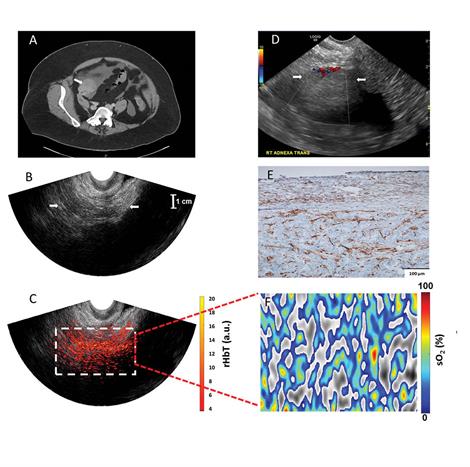

A CT image of an ovary (A), an ultrasound image (B), the combined ultrasound/photoacoustic tomography image showing vasculature in the tumor (C), soft tissue mass (D) , with numerous & extensive microvessels (E), oxygen saturation (F)

In their approach, researchers use transvaginal ultrasound to obtain information about ovarian tumors, but ultrasound lacks accuracy in diagnosis of ovarian masses, Zhu said. Photoacoustic tomography, however, gives researchers a very detailed look at the tumor's vasculature, or tumor angiogenesis, and blood oxygen saturation (sO2) by lighting up the tumor's vasculature bed and allowing for more accurate diagnoses of ovarian masses seen by ultrasound. Both tumor angiogenesis and tumor sO2 are related to tumor growth, metabolism and therapeutic response. The Washington University team is the only team using co-registered photoacoustic imaging and ultrasound to diagnose ovarian cancer.

In the pilot study, Zhu and her team created a sheath with optical fibers that wrap around a standard transvaginal ultrasound probe. The optical fibers are connected to a laser. Once the probe is inside the patient, Zhu turns the laser on, which shines through the vaginal muscle wall. With photoacoustic tomography, the light from the laser propagates, gets absorbed by the tumor and generates sound waves, revealing information about the tumor angiogenesis and sO2 inside the ultrasound-visible ovaries. A normal ovary contains a lot of collagen, Zhu said, but an ovary with invasive cancers has extensive blood vessels and lower sO2.

The team used two biomarkers to characterize the ovaries: relative total hemoglobin concentration (rHbT), which is directly related to tumor angiogenesis, and mean oxygen saturation (sO2). In this pilot study, the team found that the rHbT was 1.9 times higher for invasive epithelial cancerous ovaries, which make up 90 percent of ovarian cancers, than for normal ovaries. The mean oxygen saturation of invasive epithelial cancers was 9.1 percent lower than normal and benign ovaries. All five invasive epithelial cancerous ovaries, including two stage 1 and 2 cancers, showed extensive rHbT distribution and lower sO2.